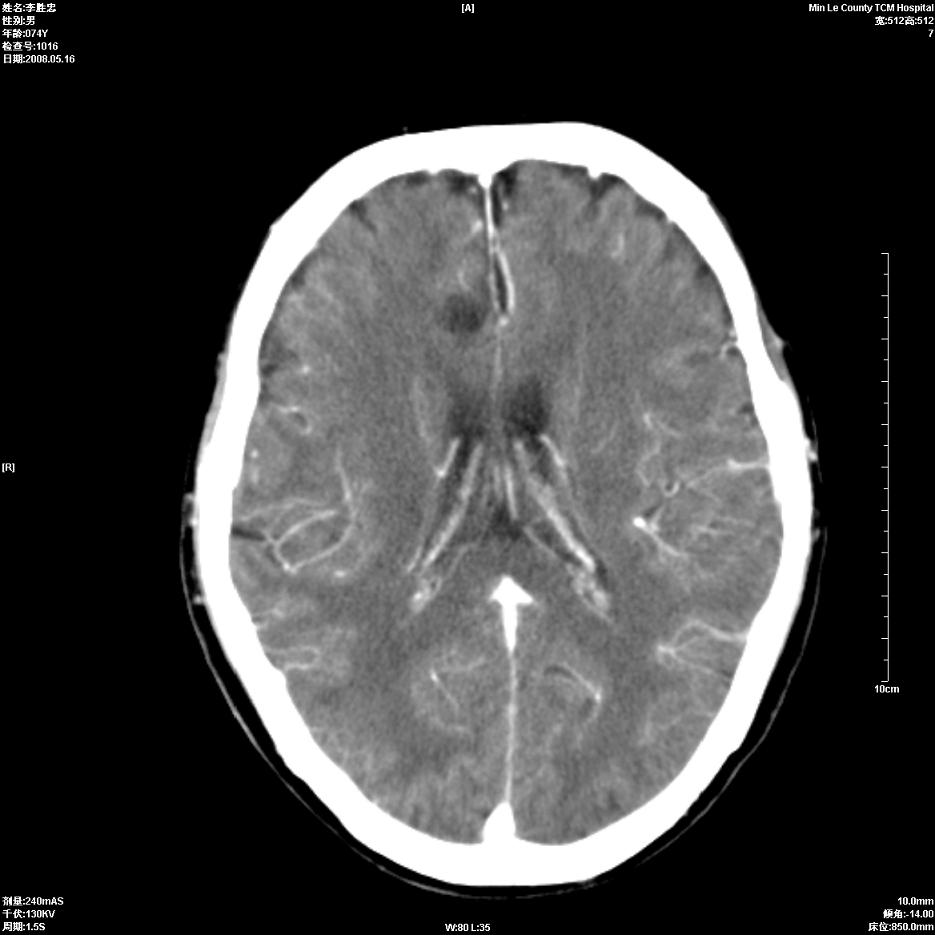

以下是引用hhcckk在2008-5-30 14:26:00的发言:[br]病灶跨中线,有占位效应,强化不明显,考虑胼胝体区低级别的星形细胞瘤可能性大,建议mr检查